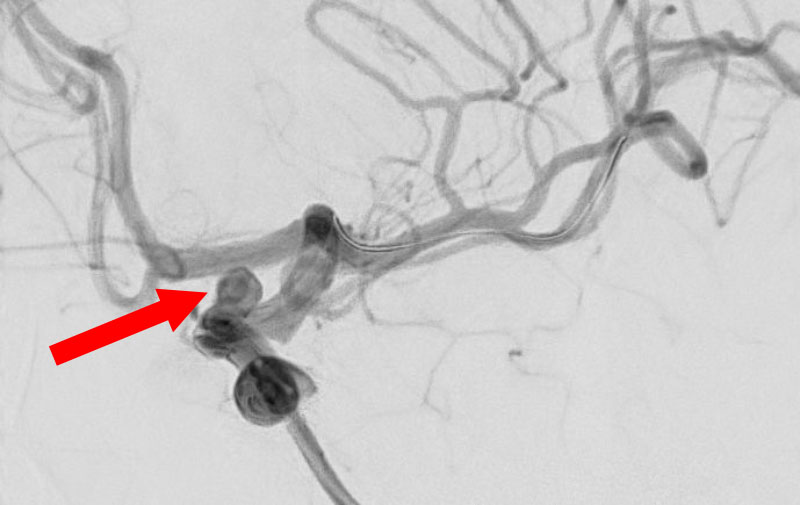

くも膜下出血

左中大脳動脈瘤破裂

40代

救急外来

No.1596 手術前